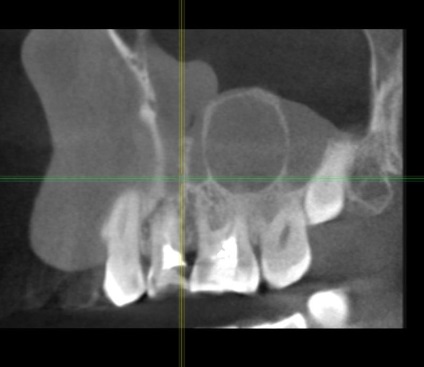

Diagnosztizálása odontogén ciszták (és más odontogén sinus léziók), két összetevője van. Először is, meg kell határozni, hogy pontosan milyen fogat volt az oka, és az állam volt az, másrészt, hogy meghatározza a helyzetét a melléküregek, beleértve a ciszta mérete és elhelyezkedése is.

A fő kutatás módszere a feltétele az arcüreg is egy X-ray, és a rendes vetülete (kétdimenziós) képeket, itt az ideje elfelejteni. Megbízhatósága és pontossága csak 25-30%.

Diagnózis a odontogenikus ciszták szükségképpen leolvasó, lehet, hogy egy multislice vagy, megint csak a kúp nyaláb tomográfia. A beolvasási terület kapjon a középső és felső harmadában az arc.